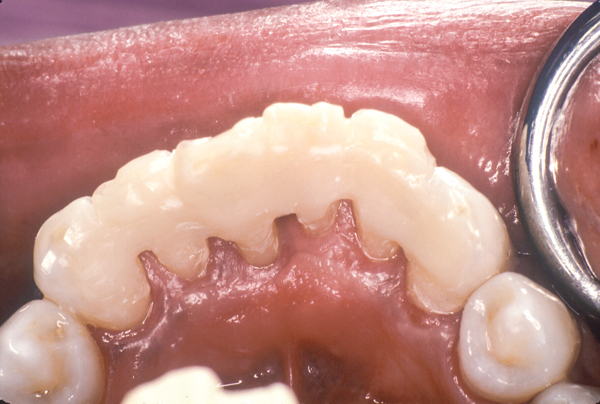

Fig 12. Mandibular canines and incisors treatment planned for fiber splinting to control tooth mobility.

Figure 12